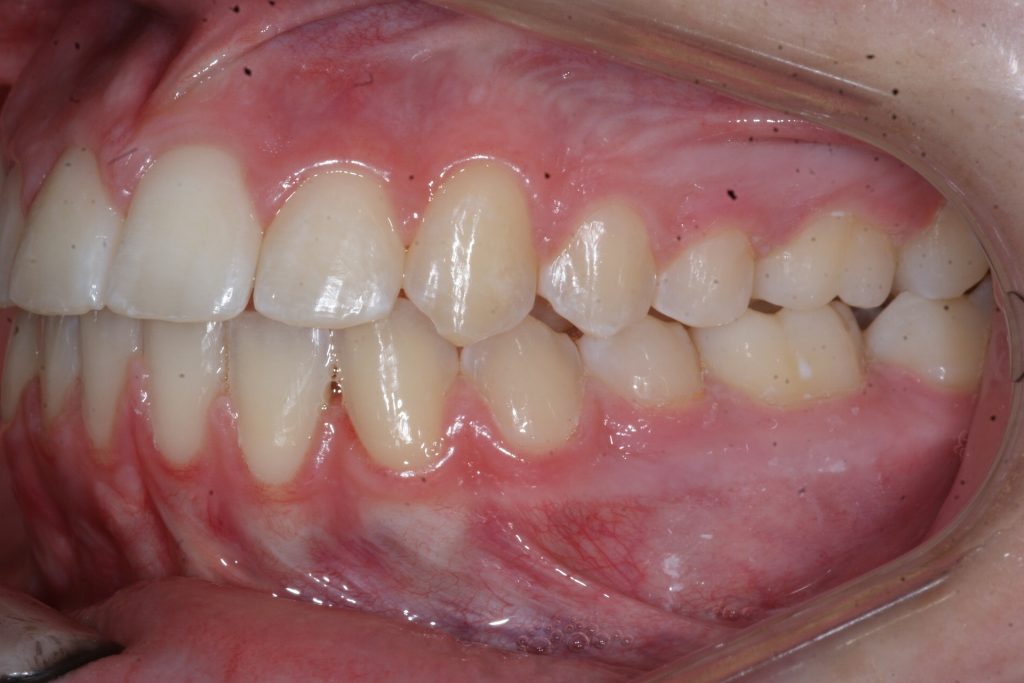

Correction d’une malocclusion de type Classe II subdivision avec canine ectopique (#14).  Des appareils fixes (boîtiers) et l’extraction d’une prémolaire (#15) furent nécessaires pour améliorer ce sourire.  Traitement chez une adolescente, réalisé en 21 mois.